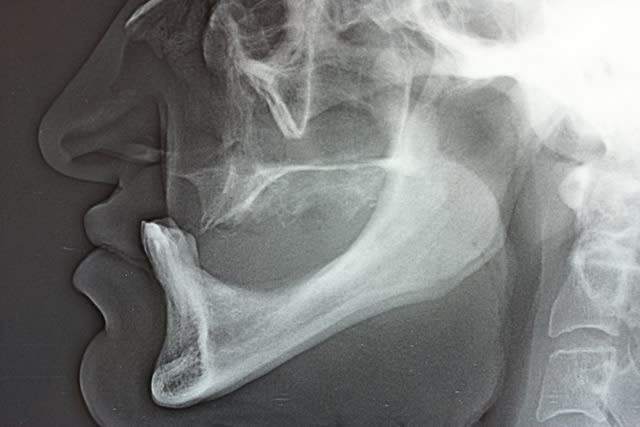

1.Bon... situation pré-extractionelle ( Je crois qu il faillait vraiment extraire )

2. Complet à essai en bouche après extraction et PRFs ds tous les alvéoles puis 3 séances d ostéotensions à venir pour le maxillaire

3. Vue sur articu

4. Télé de profil post-extractionelle

Bon la suite sera ostéotension mandibule et pose des implants mandibulaires en enfoui ds 45 j